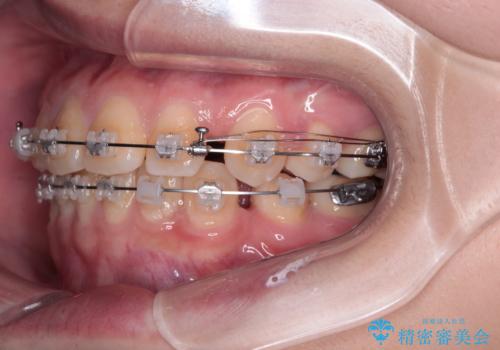

- 矯正装置

- クリアブラケット

- 転勤により東京へ移られることになり転院先を探されていた患者様です。ワイヤー矯正の途中での急な転勤なうえ、今後2~3年以内に再度転勤になる可能性もあるというご事情でした。

そのため、限られた期間内に効率よく治療を完了するために、「抜歯スペースの確実な閉鎖」「深い噛み合わせ(過蓋咬合)の改善」の2点を主軸とした治療計画を立てました。

結果的に1年半で、再度転勤になる前に治療を終えることができました。